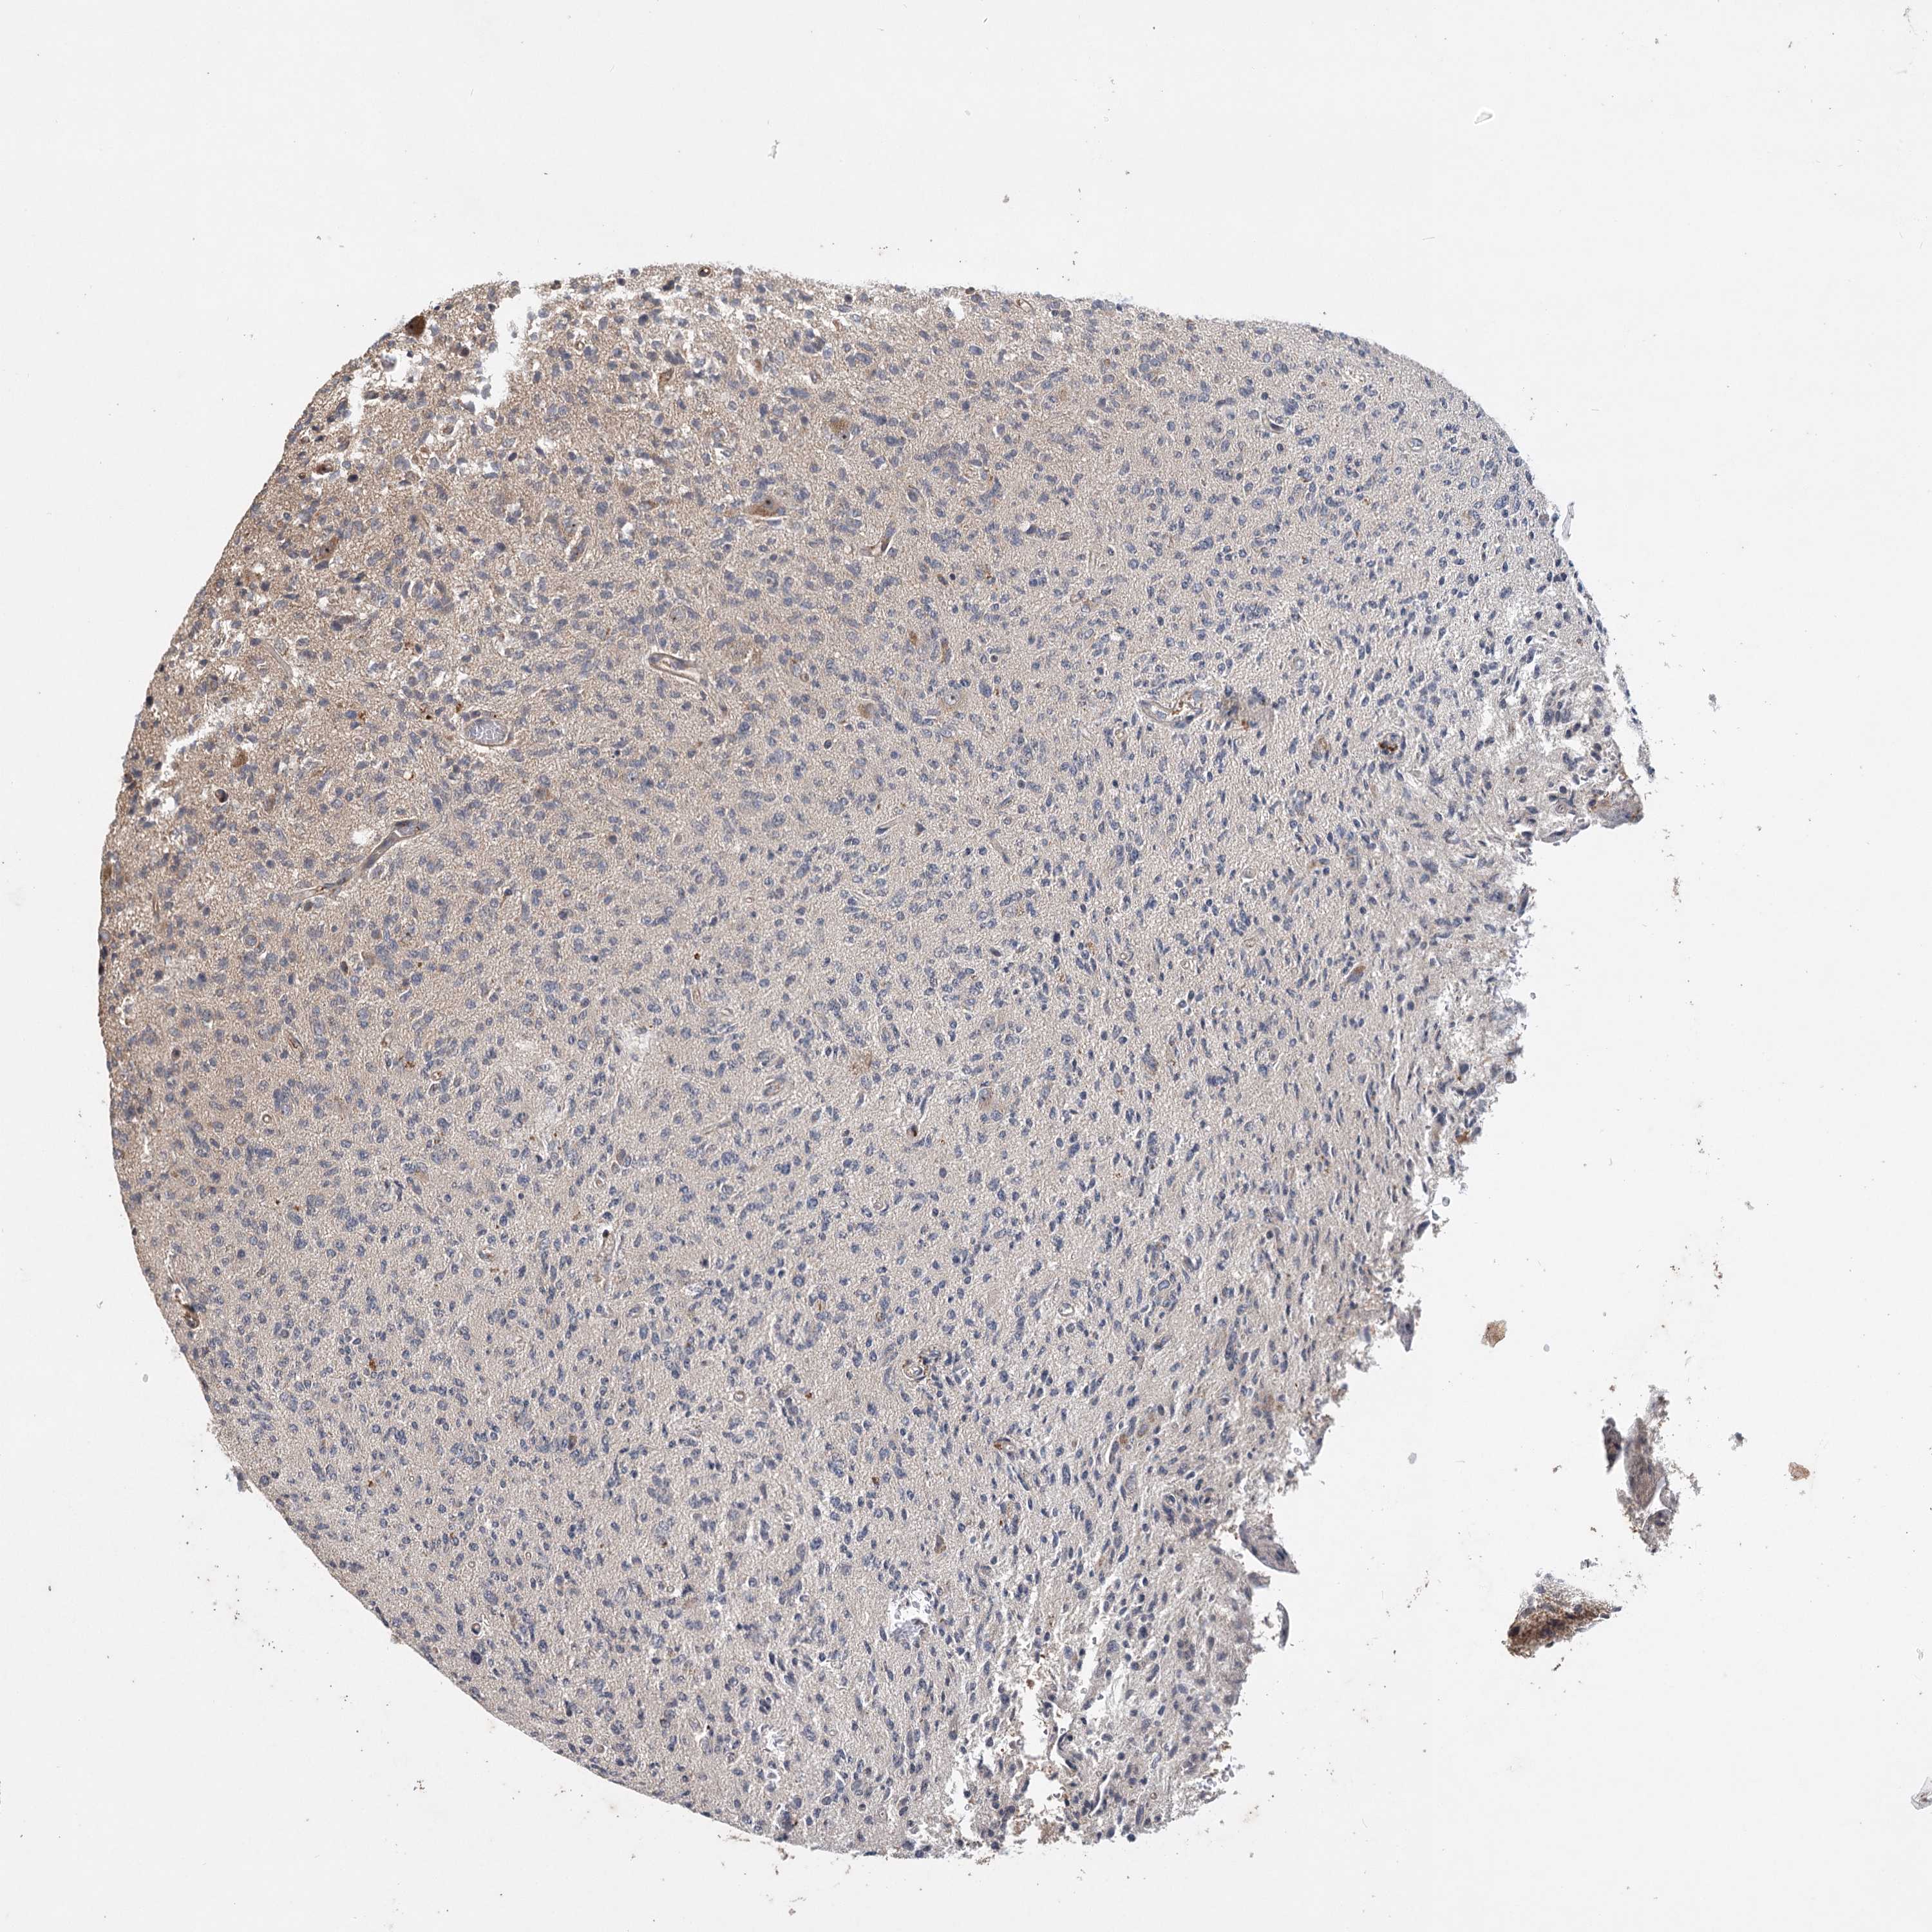

GLIOMA - Protein expressioni

A mouse-over function shows sample information and annotation data. Click on an image to view it in a full screen mode. Samples can be filtered based on level of antibody staining by selecting one or several of the following categories: high, medium, low and not detected. The assay and annotation is described here.

Note that samples used for immunohistochemistry by the Human Protein Atlas do not correspond to samples in the TCGA dataset.

Antibody stainingi

Antibody staining in the annotated cell types in the current human tissue is reported as not detected, low, medium, or high, based on conventional immunohistochemistry profiling in selected tissues. This score is based on the combination of the staining intensity and fraction of stained cells.

Each image is clickable and will lead to virtual microscopy that enables deeper exploration of all samples and also displays staining intensity scores, fraction scores and subcellular localization as well as patient and tissue information for each sample.

Antibody CAB033861

Staining

High

Medium

Low

Not detected

Intensity

Strong

Moderate

Weak

Negative

Quantity

>75%

75%-25%

<25%

None

Location

Nuclear

Cytoplasmic/membranous

Cytoplasmic/membranous,nuclear

Glioma, malignant, High grade

Glioma, malignant, Low grade

Glioblastoma, NOS